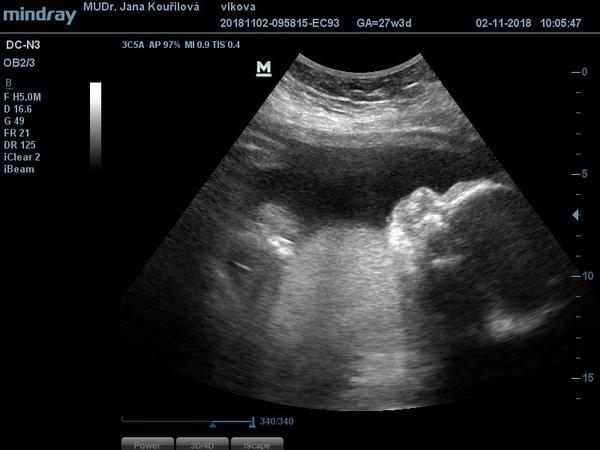

já jsem se dneska na všechno vyprdla a nešla jsem do práce, ale zůstala doma. Muž má volno, tak Jiřík nešel do školky a měli jsme rodinný den :D Dopo jsme byli u mamky orat políčko, po o jsem zazimovala zbytek kytek a teď přivezl švagr synovce, poprvé co se rozešli si ho mohl vzít, nicméně jde zítra do práce a já ho budu hlídat, ale ti dva kluci dohromady, to je pohroma....Když nedala fotku @sonisek tak zaspamuju aspoň já...náš Igoušek,..1040g....v pondělí budou výsledky krve, tak budu celý víkend nervní...